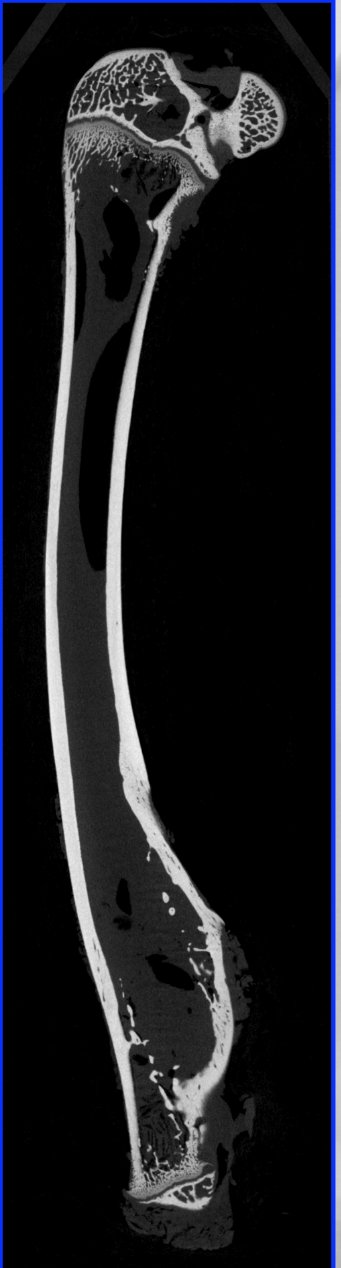

骨骼組織的三維重建

顯微 CT 可以以非破壞性的方式對骨骼組織進行三維成像,包括骨小梁的連通情況、骨密度分布等信息。這為人工骨骼的設計與制備提供了關鍵的參考,也可用于研究骨骼力學特性及其在仿生工程中的應用。